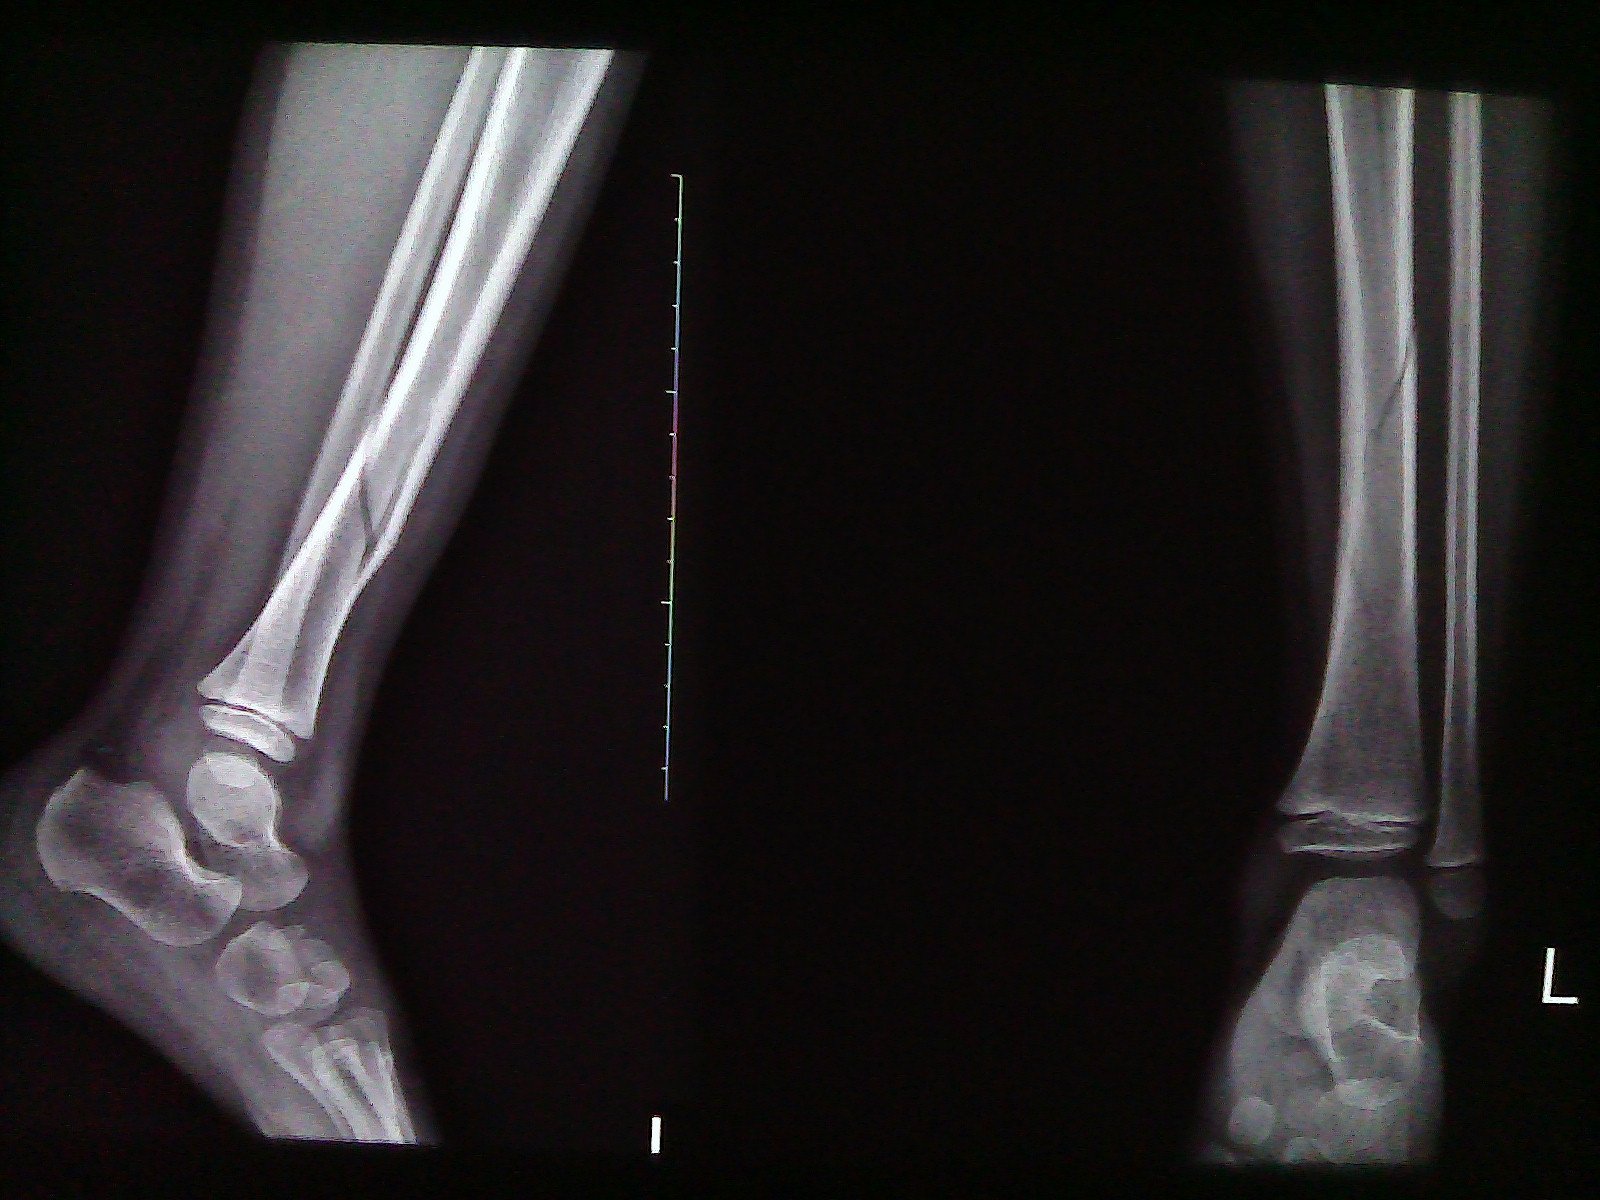

6岁小孩左胫骨下1/3段螺旋形骨折

DR报告单:左胫骨下1/3段螺旋形骨折,折远端对位对线尚可,左蜾,膝关节未见异常,其它未见异常。医生只做石膏固定治疗。请问:怎样医治好?石膏固定治疗行不行?康复要多长时间?康复要注意些什么?

您好,骨折对位比较好,可以进行保守治疗石膏固定4-6周,骨折后因为骨折处周围软组织的损伤会造成肿胀疼痛,建议卧床时抬高患肢这样有利于血液回流消肿,一般骨折完全愈合需要3个月左右,拆除石膏后进行膝关节的屈伸锻炼,拆除石膏后不要直接踩地。